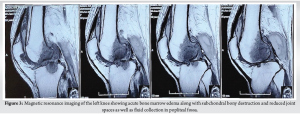

The patient was further evaluated through a series of clinical, radiological, and blood investigations. Magnetic resonance imaging (MRI) revealed acute bone marrow edema in the distal shaft and condyles of the femur and tibial plateau, subchondral bony destruction, and reduced joint spaces in the medial and lateral tibiofemoral compartments. In addition, loculated fluid collection in the popliteal fossa and mild collection in the suprapatellar bursa were noted (Fig. 3), confirming an inflammatory pathology.